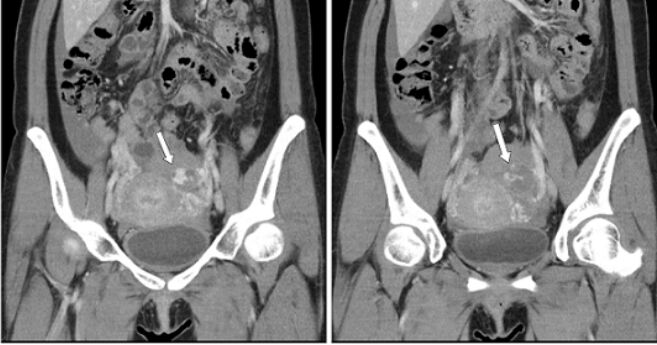

73.28歲女性主訴腹部突然劇痛,注射顯影劑後電腦斷層檢查呈現如圖,箭號所指之病灶,下列何項診斷最不可能?(A)異位妊娠破裂(B)腹腔血腫(C)子宮內膜異位(D)急性輸卵管破裂出血